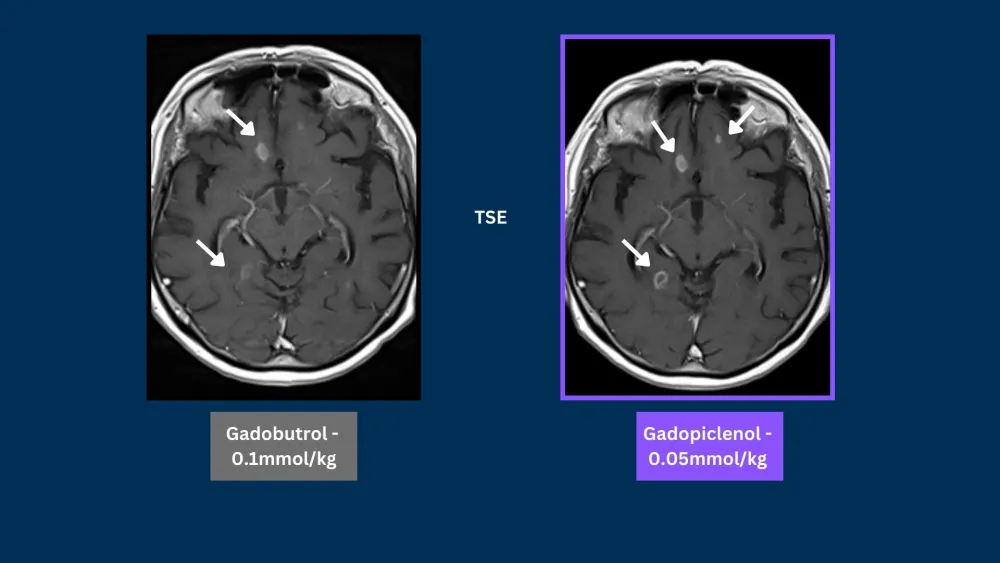

Phase III clinical trials, in CNS and Body, demonstrated that gadopiclenol at a dose of 0.05 mmol/kg was noninferior to gadobutrol at a dose of 0.1 mmol/kg in terms of lesion visualization.5,6

SE = Spin Echo, GRE = Gradient Echo, 3DGRE = 3D Gradient Echo, TSE = Turbo Spin Echo

Phase III PICTURE trial in CNS demonstrated that gadopiclenol at a dose of 0.05 mmol/kg was noninferior to gadobutrol at a dose of 0.1 mmol/kg in terms of lesion visualization.5